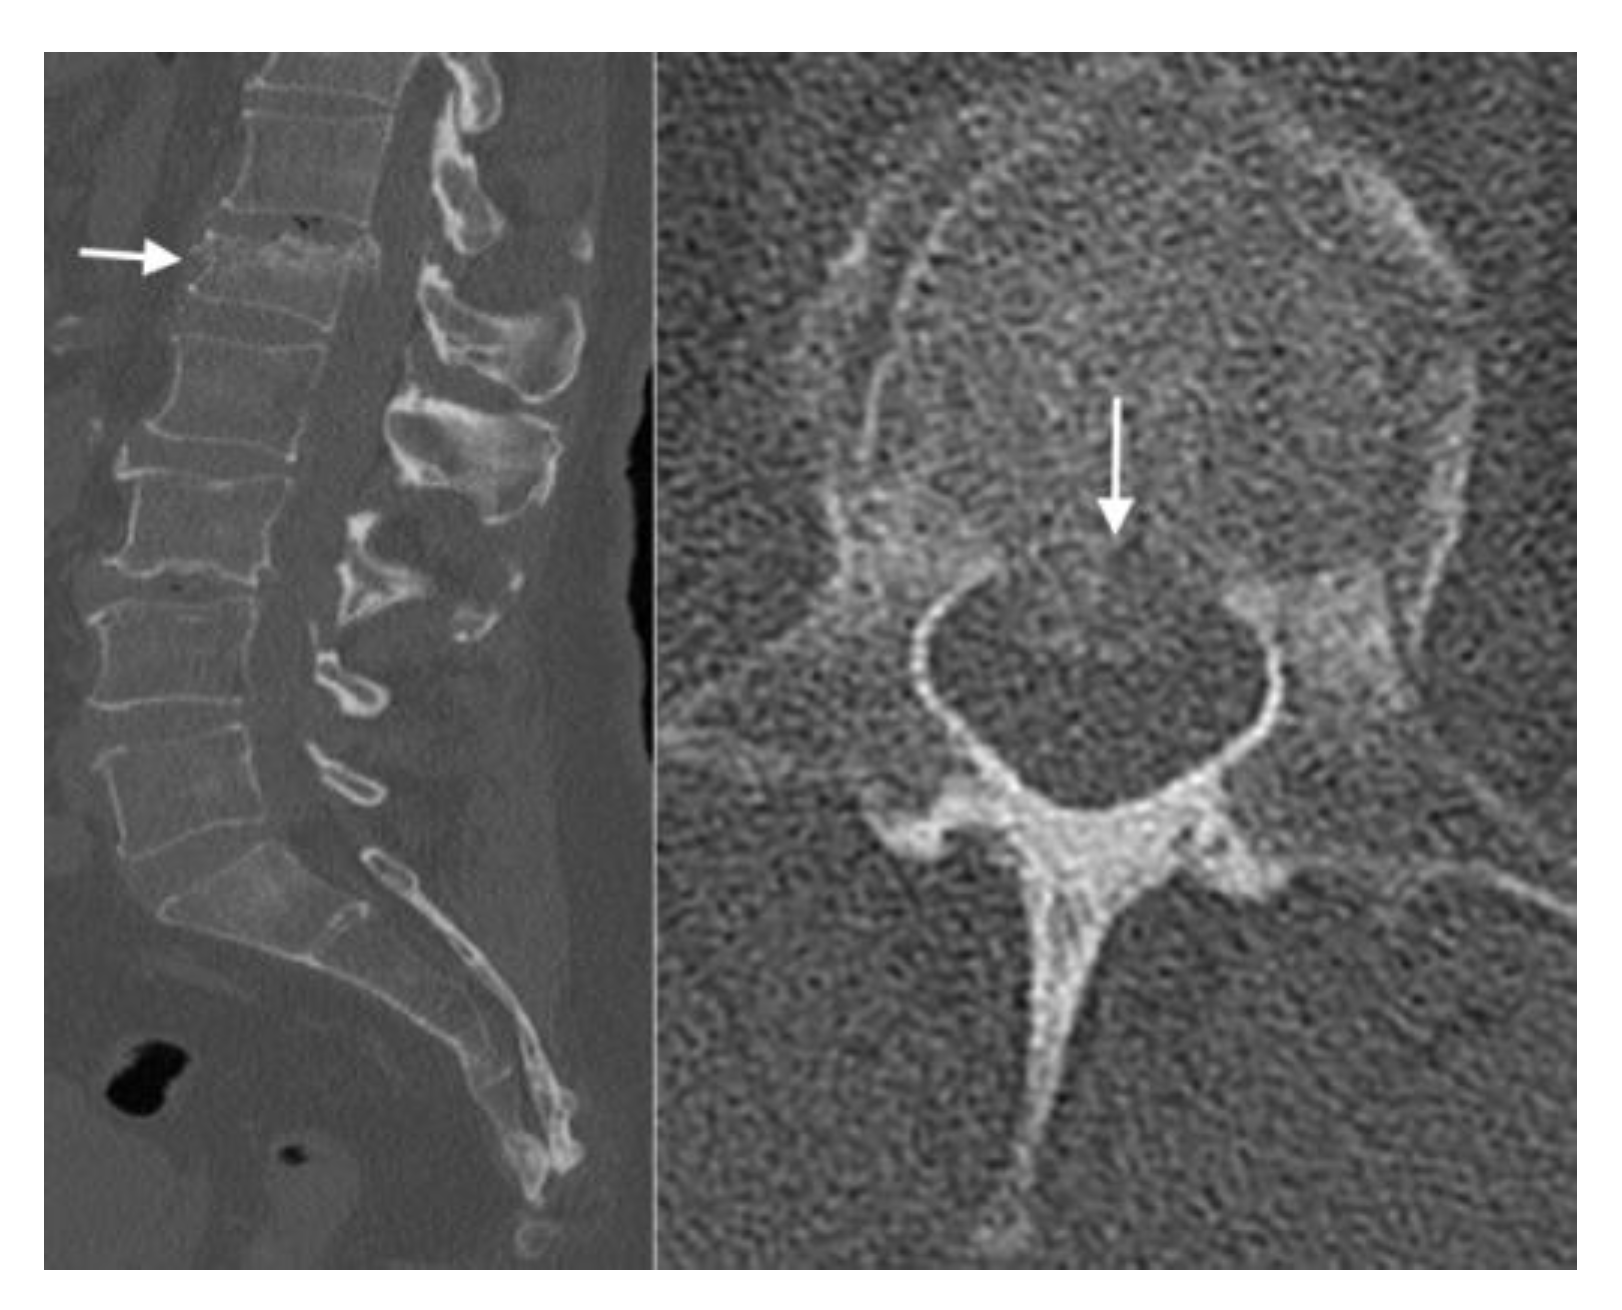

4.2. CT Scans